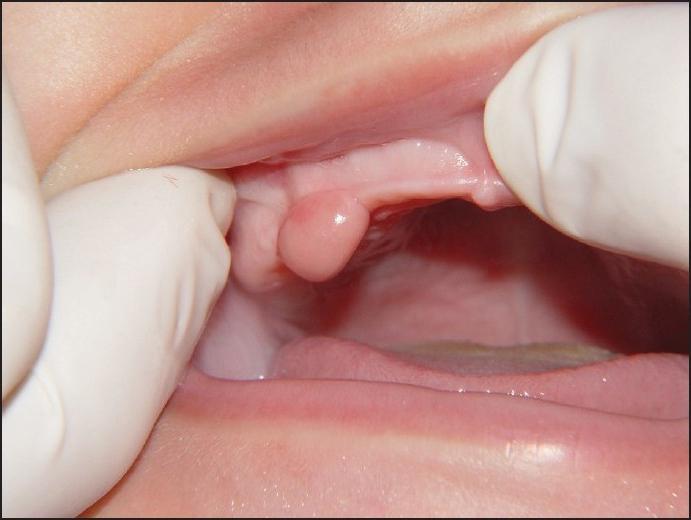

У детей

Детский возраст – это тот период, когда патология обнаруживает себя и развивается очень быстро. Такое стремительное ее развитие обусловлено высокой степенью травматичности детской слизистой и десны.

Нарост обычно диагностируется в период появления молочных зубов, когда дети, тянет в рот окружающие их предметы, повреждают десны. Защитная функция организма в это время сформирована не полностью, и на месте травмирования начинает развиваться опухоль. Чаще выявляется ангиоматозная разновидность эпулиса.

Второй «опасный» период, когда присутствует высокая вероятность разрастания тканей – это подростковый период, а точнее, гормональная перестройка организма при половом созревании. Подобное нарушение может встречаться и у девушек, неправильно принимающих гормональные препараты.

Для детского возраста характерно перетекание одного вида опухоли в другой. Так, заболевание может начаться с гранулематозной разновидности, перейти в ангиоматозный, а затем в фиброзный. У детей присутствует высокий процент рецидивирования состояния – около 15% случаев.

Важно: родителям при его обнаружении необходимо незамедлительно обратиться к врачу. Это нужно для предотвращения его разрастания и дальнейшего распространения.